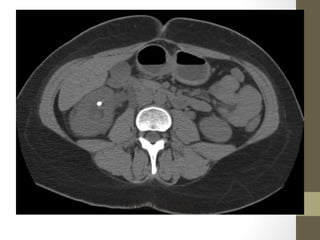

Psoas Abscess

Retroperitoneal Abscess

Radiology- CT Scan

• Detect leaking AAA (in stable patient)

• Evaluate for renal calculi, appendicitis, perforation (free air),

diverticulitis, abscess, mesenteric ischemia, masses, obstruction